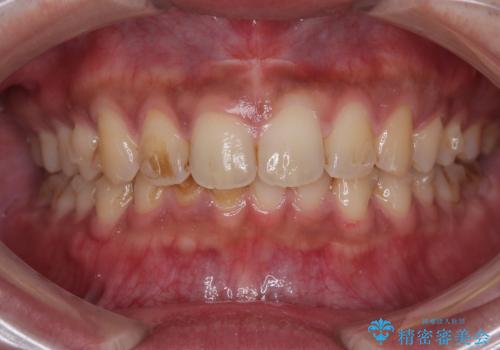

- 上の前歯の正中離開(すきっ歯)と、下顎前歯部の叢生(デコボコ)を主訴に来院された患者様の症例です。

「目立ちにくい装置で治療したい」とのご希望があり、透明のマウスピース矯正であるインビザラインを用いて矯正治療を行いました。